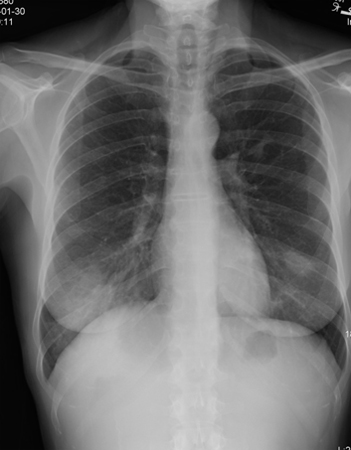

Chest x-ray is the initial investigation of choice and usually shows patchy infiltrates.[48][49] In many cases, patients are misdiagnosed with a community acquired pneumonia and are treated with a course of antibiotics.

Quite often, the symptoms persist and the chest x-ray worsens, usually with enlargement of the patchy infiltrates. In some situations, waxing and waning opacities may develop over a couple of weeks.

[Figure caption and citation for the preceding image starts]: Chest x-ray showing bilateral patchy infiltratesFrom the collection of Gary R. Epler, MD [Citation ends].